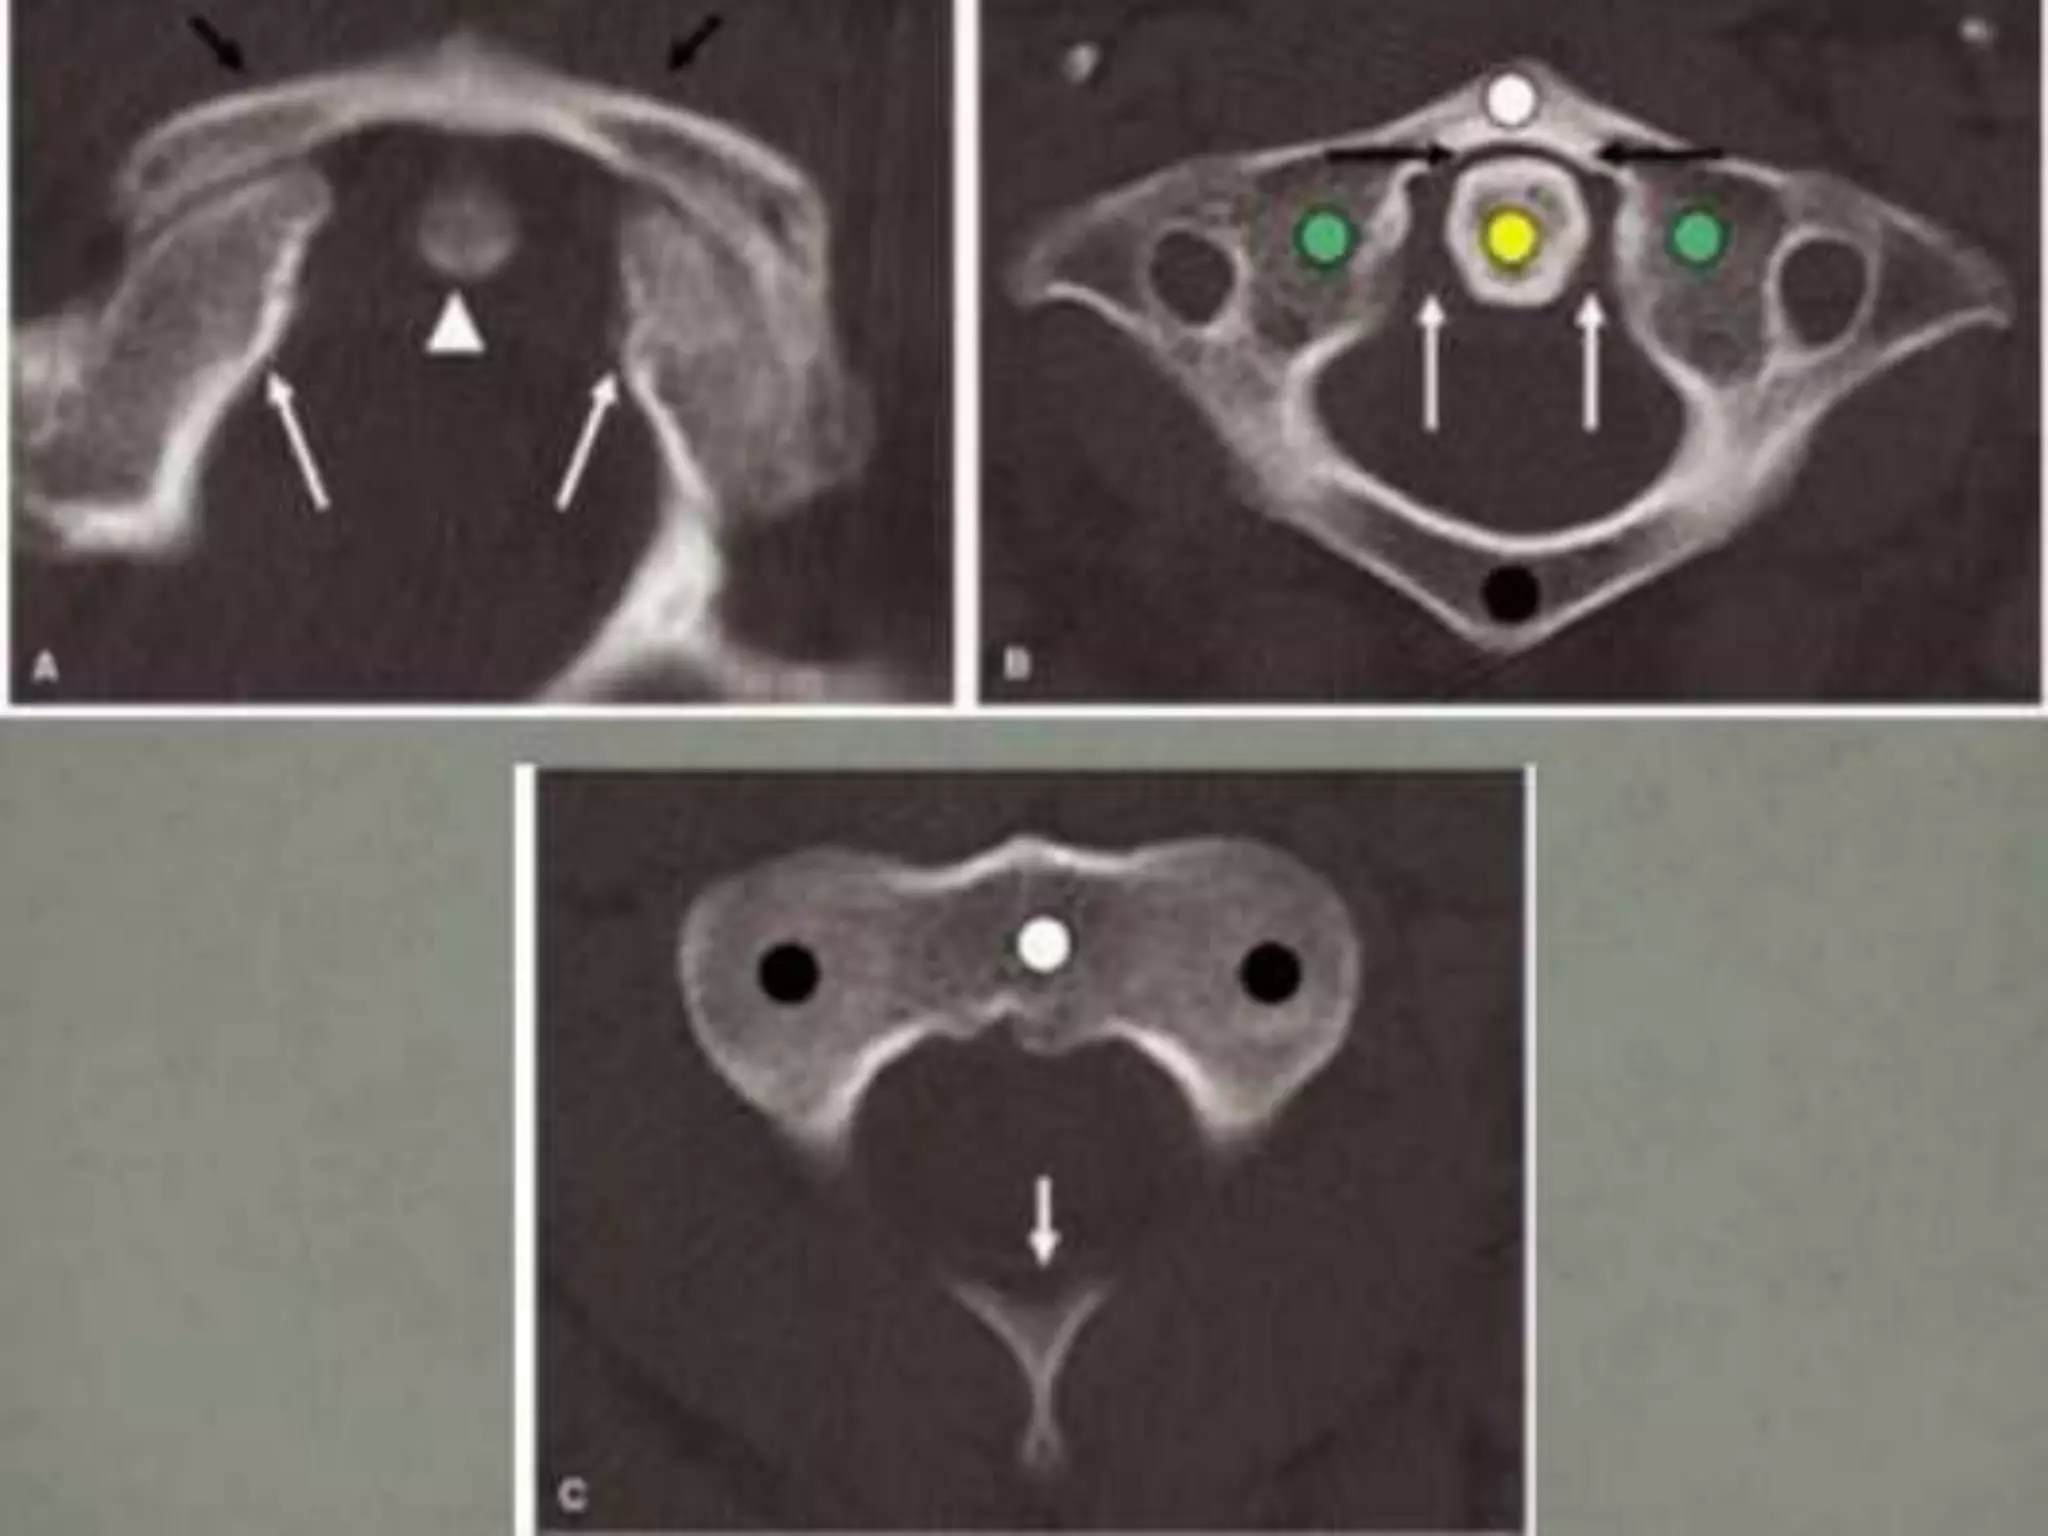

Vertical Compression(Axial Load).

•Force delivered to top of skull

through the occipital condyles to

the cervical spine at the instant

that the cervical spine is straight

• Injury Patterns:

1. Jefferson fracture.

2. Burst fracture.

Jefferson Fracture:

• Splitting of C1 ring with fracture of both the

anterior and posterior arch

– may result from a single break in each arch

(anterior and posterior)

– bilateral or unilateral

• Centripetal displacement fragments

• 50% associated fractures

– 33% = axis fractures

• no neurologic deficit

• Transverse atlantal ligament intact or not

• UNSTABLE

Vertical Compression(Axial Load). •Force delivered to top of skull through the occipital condyles to the cervical spine at the instant that the cervical spine is straight • Injury Patterns: 1. Jefferson fracture. 2. Burst fracture.

• 41.

Jefferson Fracture: •Splitting of C1 ring with fracture of both the anterior and posterior arch – may result from a single break in each arch (anterior and posterior) – bilateral or unilateral • Centripetal displacement fragments • 50% associated fractures – 33% = axis fractures • no neurologic deficit • Transverse atlantal ligament intact or not • UNSTABLE